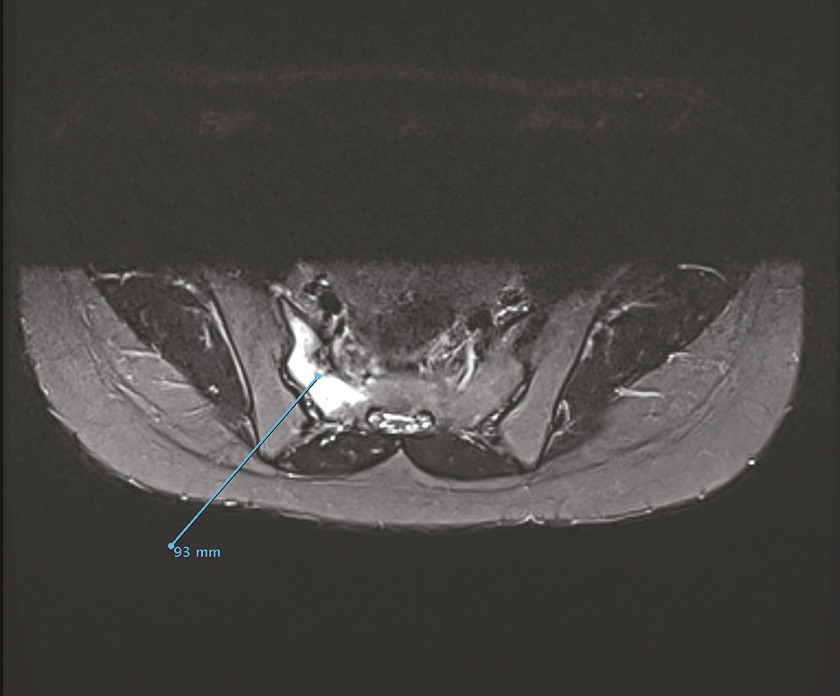

Engagée depuis 2 mois, cette jeune militaire consultait pour des paresthésies des orteils, sans notion de traumatisme aigu. Sédentaire auparavant, elle n’avait aucun antécédent particulier. Son indice de masse corporelle était de 20 kg/m2. L’examen notait une douleur neurogène avec trouble des sensibilités prédominant à l’extrémité du pied droit, sans syndrome radiculaire ni rachidien, d’horaire non mécanique. Le test de Faber était positif. Réalisée en seconde intention, l’IRM du bassin (v. figures) montrait une fracture de contrainte de l’aileron sacré droit. Le bilan biologique était sans particularité. Une cure courte d’anti-inflammatoires non stéroïdiens et la limitation au minimum des activités physiques entraînaient la guérison en 8 semaines.